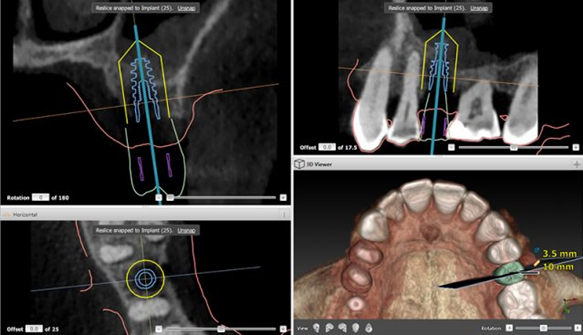

Le X-Guide est un système de navigation en 3D pour le chirurgien, rendant la pose d’implants dentaires plus précise et sécuritaire que jamais auparavant.

Le chirurgien voit dorénavant en temps réel l’axe d’implantation et la profondeur de l’implant, ce qui lui permet de s’assurer que l’implant est placé exactement comme il l’avait planifié.

Il s’agit d’un GPS pour chirurgien qui lui permet de suivre la voie tracée !